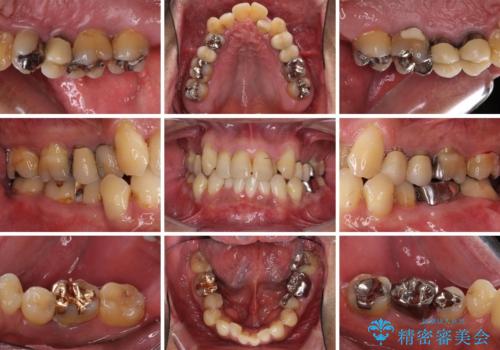

- 前歯がのデコボコや、奥歯に咬んだときに痛みがあるとのことで来院された患者様です。

全体的に問題が多く、全てをしっかりと治療したいとのことでした。

全体的に中等度の歯周病と診断されたため、歯周外科処置やインプラントによる咬合回復から進めて行き、矯正治療による歯列改善を行った後にオールセラミッククラウンにて補綴することとしました。